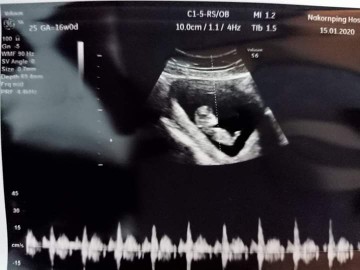

ขอดูใบซาวเด็ก ผช. ของแม่ๆ หน่อยค่ะ ?

ในภาพเป็น ผช ใช่ไหมค่ะ พอดีหมอขอชัวร์ๆ เดือนหน้า เลยสอบถามแม่ๆ ที่มีประสบการณ์ลูกชาย หน่อยค่ะ ?ขอดูใบอัตตลาซาวเด็ก ผช . หน่อยจร้าาา? ถาพไม่ชัดเพราะถ่าย VDO มาจร้า ??

ผช คะ

BOY